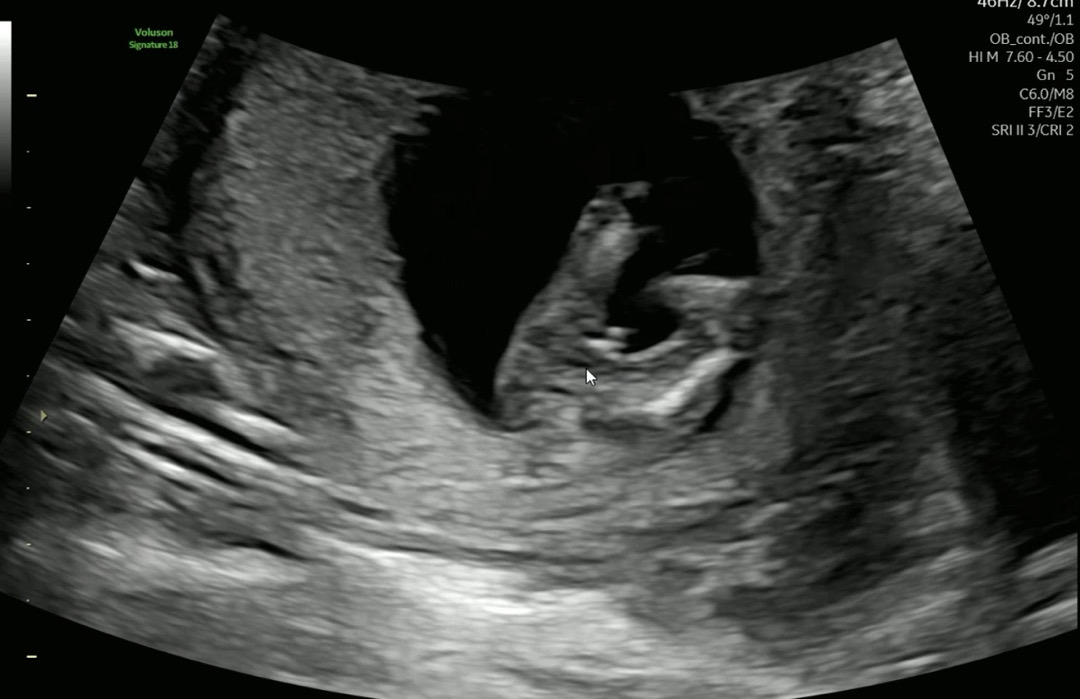

13주 아들 존재감😂심쿵주의🩵

니프티 해서 아들인건 알고 있었지만 어제 춈파에서 이렇게 존재감 뿜뿜 해주더라구요😂 아들을 기다렸어서 🌶️ 뽝!! 만들어 놓은게 너무 귀엽기도 하고 기특하더라구요..😂😂 성별 알고 나니까 쇼핑하는게 너무 재밌어요😆